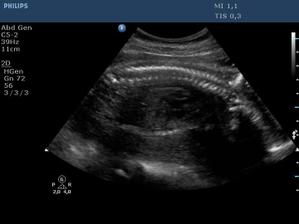

Ultrazvuk miminka - 24 týden

Z "menší protekce" u pana primáře Radiodiagnostického oddělení jsme mohli na soukromou "špionáž" naší krásné holčičky... (Pan doktor je už třetí, kdo hádá holčičku a po pravdě s tím přístrojem, co má k dispozici, bylo naprosto zřetelně vidět, že tam žádný pytlík není! :o)) Natočil nám i několik videí, kde ta naše šibalka zívala a dvakrát na nás dokonce vyplazovala jazyk. ;o)